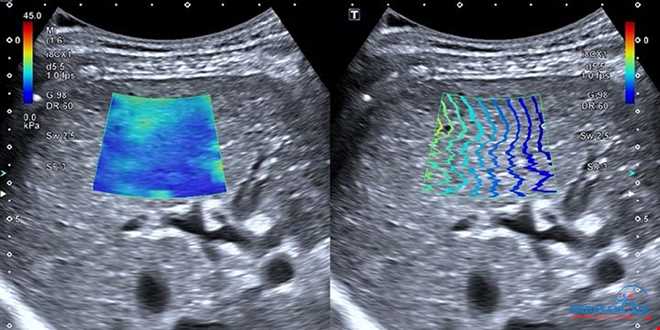

فیبرواسکن با Shear Wave Elastography در رادیولوژی اکباتان

در رادیولوژی اکباتان، فیبرواسکن با فناوری پیشرفته Shear Wave Elastography انجام می‌شود که:

دقت اندازه‌گیری سختی بافت کبد را افزایش می‌دهد

قابلیت ارزیابی تصویری بخش‌های مختلف کبد را فراهم می‌کند

خطاهای ناشی از چاقی یا وضعیت نامناسب بدن را کاهش می‌دهد

نتایج را همراه با سونوگرافی کبدی ارائه می‌دهد